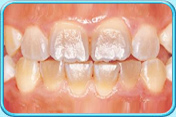

牙齒表面有啡黃或白斑

初期蛀牙

牙科醫生可於牙齒表面塗上牙面氟化物劑,使初期蛀牙得以修復

牙齒發育時受感染或氟斑牙

以複合樹脂補牙、做貼面修復治療或鑲配人造牙冠

填上複合樹脂後的牙齒